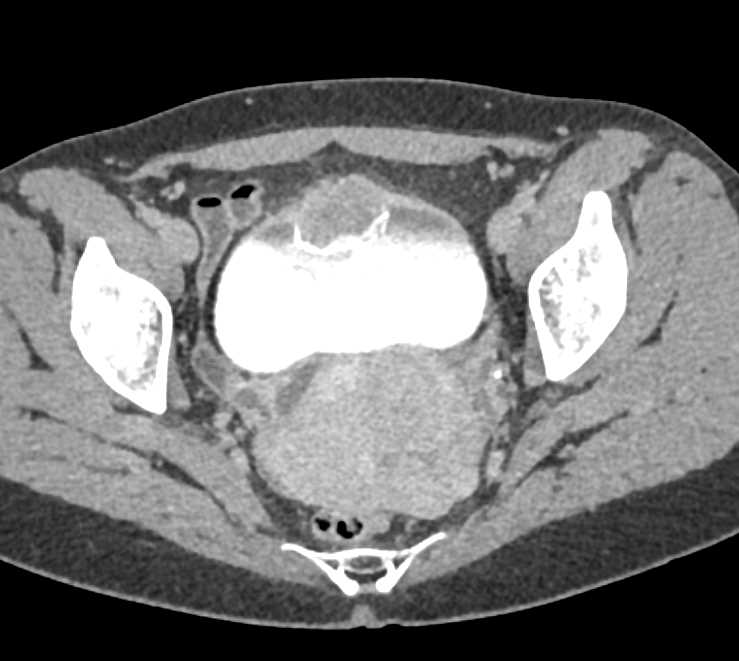

Urachal Carcinoma of the Bladder